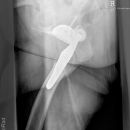

pertrochantäre Femurfraktur